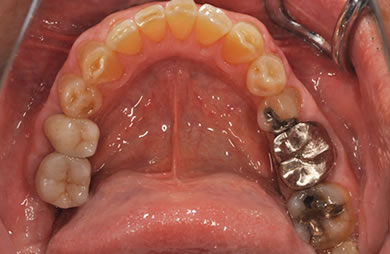

治療後

• 治療後